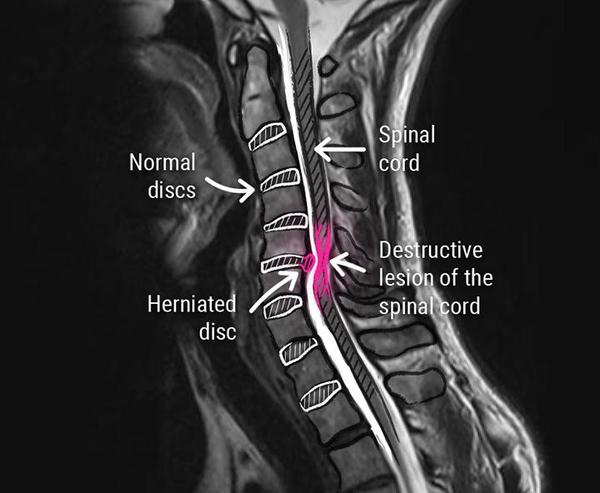

When you’re dealing with numbness, tingling, shooting pain, weakness, or stubborn neck/low back issues, the right imaging can change everything. An MRI can help us:

See disc bulges, herniations, stenosis, and nerve compression that X-rays can’t show.

Confirm the true cause of your pain so treatment is targeted—not guesswork.

Decide faster whether you’re a candidate for non-surgical spinal decompression, chiropractic care, laser therapy, or co-management with another specialist.